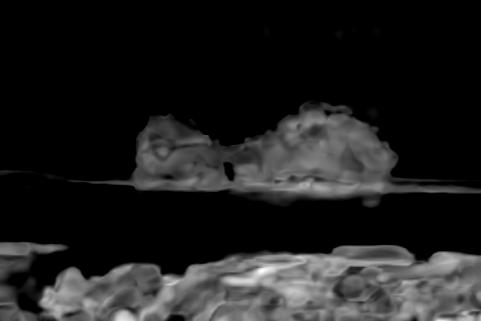

Refer to caption

(a) Original Image

(b) SNIC, DICE 81.6%

(c) EA, DICE 81.3%

(d) Ours, DICE 87.9%

(e) Ground Truth

Figure 7: Qualitative Comparison of Superpixel Algorithms on an image from DeepVess.

The results in Table 1 show that our approach performs best across other superpixel algorithms in an end-to-end segmentation pipeline. Based on this observation we conclude that the slight drop in compactness we observed in the natural image experiments with respect to EA does not affect the quality of post-processing. Moreover, the results stress our method’s robustness with respect to noise. It is also worth noting that it closely matches the performance of a trained neural networkand the second human annotation on this dataset. While the Double-DIP seems to work on natural images with a saliency estimate, it does not converge on noisy microscopic data which is why we decided to stop the optimization after 500 steps. In Figure 7 we can see superpixel based foreground predictions generated from a DeepVess slice. While SNIC fails to match superpixels to vessel structures and overfits to noise artifacts, EA and our method produce smoother superpixels. However, the Deep Decoder is better at detecting low-intensity shapes and adhering to vessel boundaries, as it can be seen around the ground truth objects in the top left part in Figure 7, which is why the segmentation pipeline works best with our method as a superpixel generator.